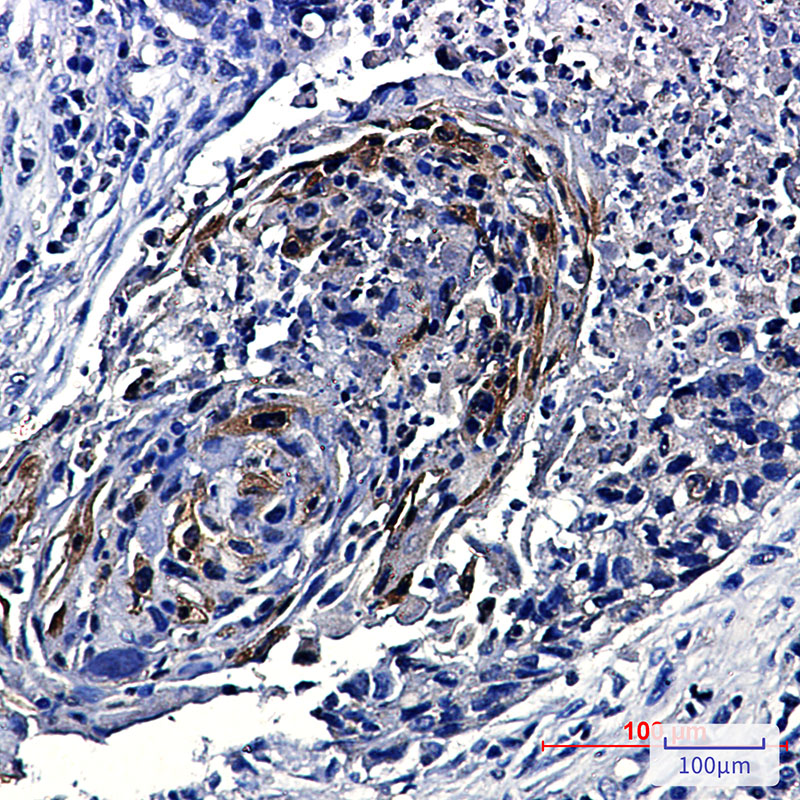

- Immunohistochemistry analysis of paraffin-embedded Human lung cancer using Phospho-mTOR (Ser2448) antibody.High-pressure and temperature Sodium Citrate pH 6.0 was used for antigen retrieval.